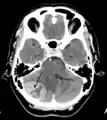

Tumor de la fosa posterior que provoca efecto de masa y desplazamiento del cuarto ventrículo.